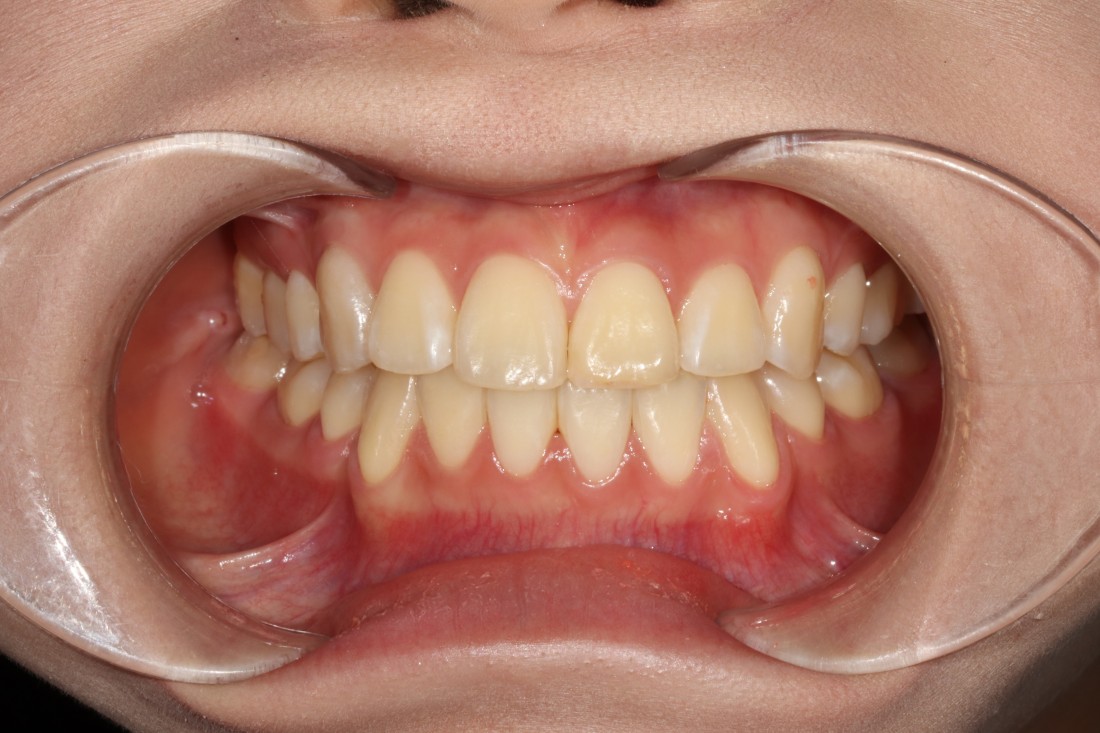

수완동 교정치과에서는

교정 진료에 필요한

모든 비용을 포함한 금액으로

치아교정을 진행합니다.

교정 전 3차원 105항목 정밀검사 비용,

교정장치 (100% 정품 클리피씨) 비용,

전문의 발치비용,

월 진료비용,

교정 후 유지장치 비용 등

다양한 항목의 교정진료 항목 비용을

모두 포함한 금액으로

합리적인 가격의 수완동 교정진료를

진행하고 있습니다.